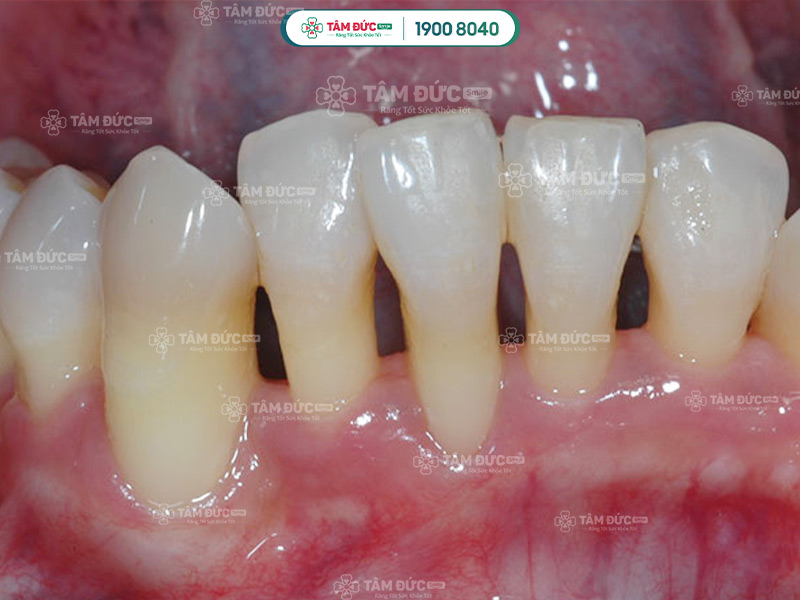

3.3. Làm cho răng trông dài hơn

Vùng lợi xung quanh bị tụt xuống sẽ làm cho thân răng trồng dài hơn. Răng nhạy cảm rất dễ bị bám màu hoặc tạo thành kẽ hở lớn với răng còn lại. Điều này sẽ làm ảnh hưởng nghiêm trọng đến thẩm mỹ nụ cười.

Răng có vẻ dài hơn khi Quý khách bị tụt lợi chân răng